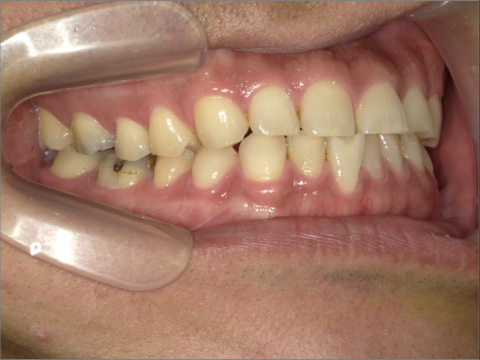

ご年齢 35歳男性

治療期間 2022/08/22〜2023/03/24(1年5ヶ月)

診断 110,000円(税込)

アライナー 550,000円(税込)

リテーナー 55,000円(税込)

BEFORE

AFTER